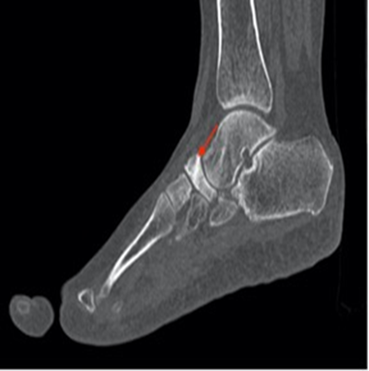

Ct scan is

also useful for diagnosis and plays an important role in the preoperative

assessment by evaluating the bone’s structure and their mineralization (figures 3,4).

Figure 3. Sagittal ct scan of the forefoot demonstrating the

comma aspect of the navicular bone (red arrow)